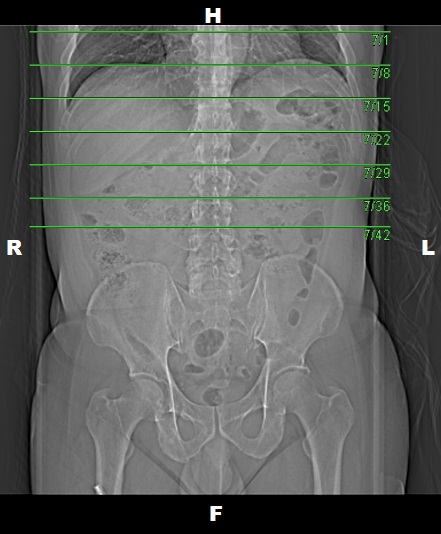

Topogram

• Position the patient in head first supine position.

• Align the patient in Mid-Sagittal plane of the table.

• Position the transverse laser light beam at the level of mid of sternum to start the topogram.

Topogram Parameters

• Topogram length: 512 mm

• Slice: 0.6 mm

• Scanning direction: Craniocoudal

• Tube position: Top

• Stop the topogram scanning when the scanning reach / pass over the inferior ischial ramus.

Non Contrast

• Plan the Scan FOV (SFOV) box at topogram image.

• Set the top line at the level of upper diaphragm.

• Set the bottom line at the level of inferior ischial ramus.

• Ensure the lateral line to cover patient’s body outline.

• Remind the patient before scanning as the breathing instruction will be given.